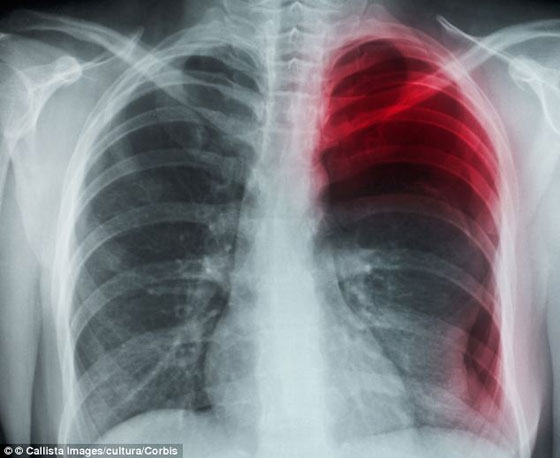

ولم يعر الرجل (26 عاماً) اهتماماً للألم الذي شعر به في البداية، ولكنه سرعان ما قصد الطبيب حين ازداد الألم إلى درجة أنه بات عاجزاً عن التنفس. وقال الأطباء إنه أصيب بتمزق "جيب هوائي" في الرئة، وتسبب ذلك في تسرب الهواء إلى التجويف المحيط بها.

عانى الشخص من حالة استرواح الصدر العفوي، والتي تحصل عندما ينحصر الهواء

يجانب الرئة، الحالة شائعة لدى الأشخاص صغار العمر طويلي القامة.